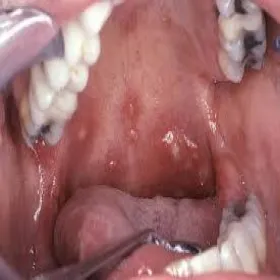

Choroba bostonka owrzodzenie jamy ustnej

owrzodzenie jamy ustnej